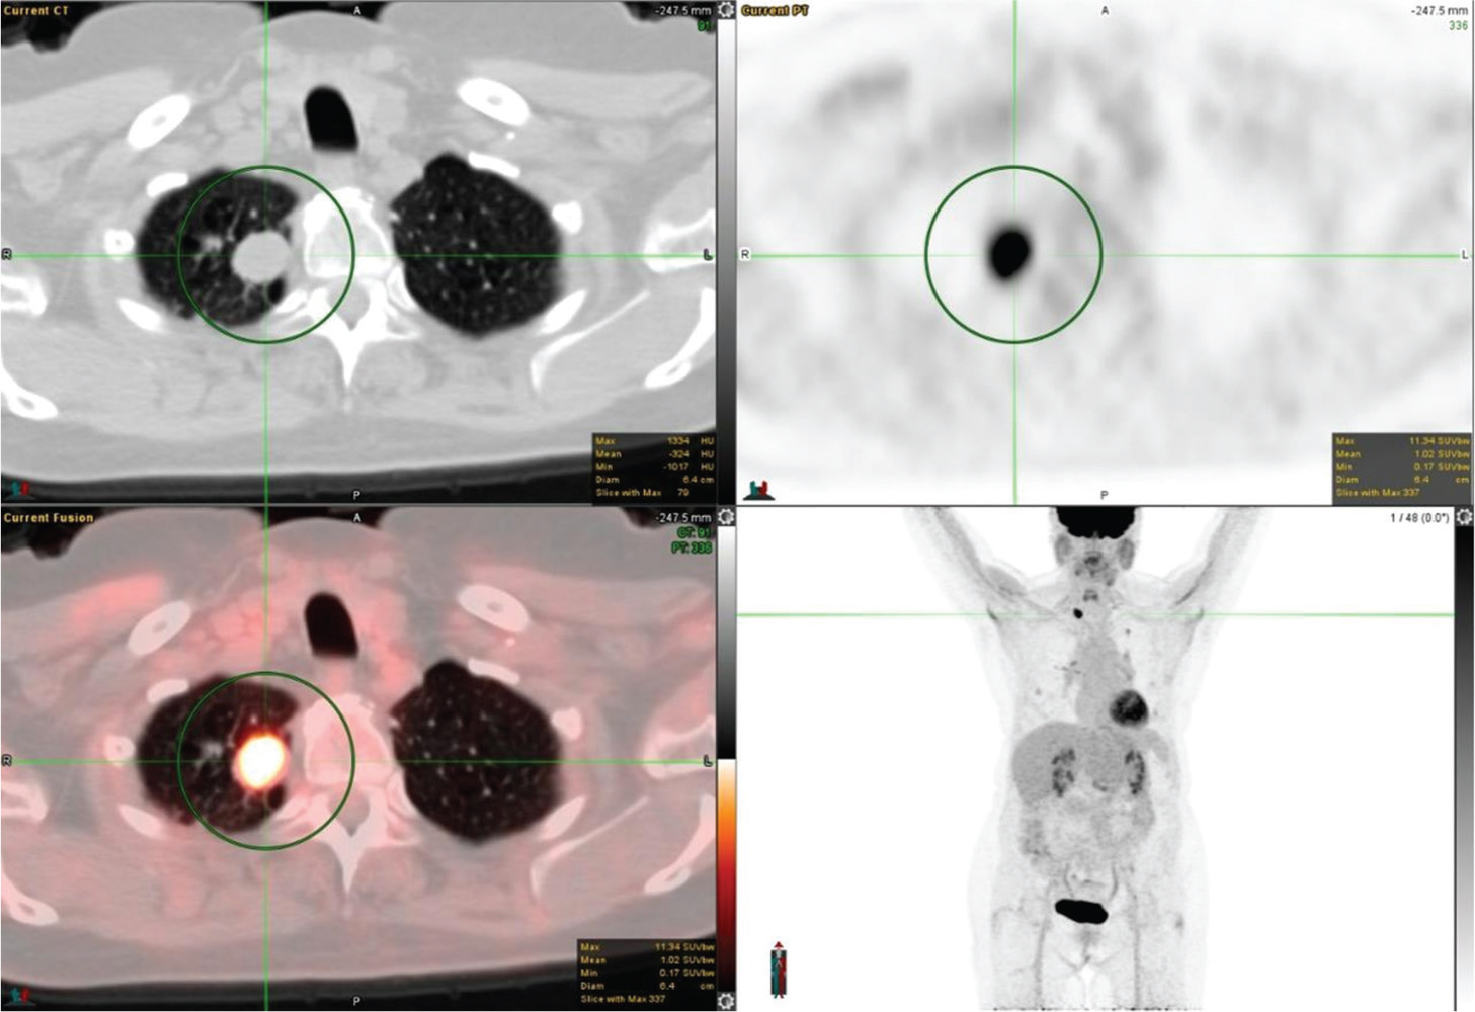

Staging

Accurate staging of lung cancer is mandatory after the diagnosis for appropriate patient management. Many guidelines such as the National Comprehensive Cancer Network (NCCN), the ESMO Clinical Practice Guidelines, the American College of Radiology Appropriateness Criteria, the guidelines of the Society of Nuclear Medicine and Molecular Imaging, and the guidelines of the American College of Chest Physicians recommend 18F-FDG PET/CT for evaluation of patients with stage I to stage IV NSCLC (2124). For the staging of NSCLC, the most standardized and recognized system is the TNM system, where T denotes the size of the primary tumor, its location and level of invasion; N indicates the status of regional lymph nodes; and M refers to the presence or absence of more distal metastases (25). FDG PET/CT plays a vital role in the staging of T, N, and M of lung cancer and an example of FDG avid primary and metastatic tumors is shown in Figure 4.

Fig 4

Figure 4. Right upper lobe lung mass that was pathologically confirmed as poorly differentiated non-small cell lung cancer. FDG PET/CT images include axial CT (top left panel), axial PET (top right panel), fused axial PET/CT (bottom left panel), and maximum intensity projection (MIP) PET image (bottom right panel). In the green circle, there is a spiculated pleural based right upper lobe mass with surrounding interlobular septal thickening on CT with intense FDG uptake on PET. There are additional FDG-avid metastatic foci within the lungs and mediastinal lymph nodes.